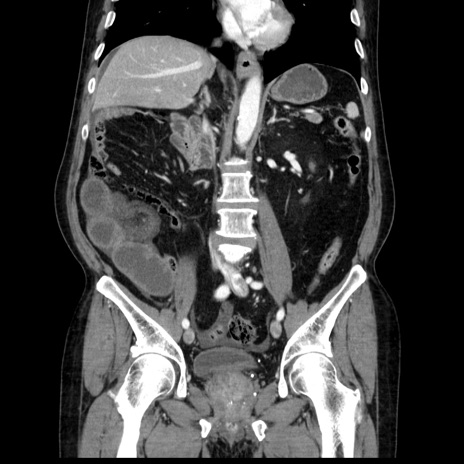

症例30(冠状断像)

【症例】80歳代男性

【主訴】臍周囲痛

【現病歴】約6時間前から臍下部痛が出現。次第に腹部膨隆・背部痛も生じてきたため来院。背部痛の場所は変化しない。

【身体所見】意識清明、BT 36.3℃、BP  131/87mmHg、P 87bpm、SpO2 100%(RA)、臍周囲自発痛・圧痛あり、反跳痛なし、自発痛部位に一致して板状硬あり、腹部膨隆、腸雑音減弱、CVA tenderness両側陰性。

【データ】WBC 19600、CRP 0.33